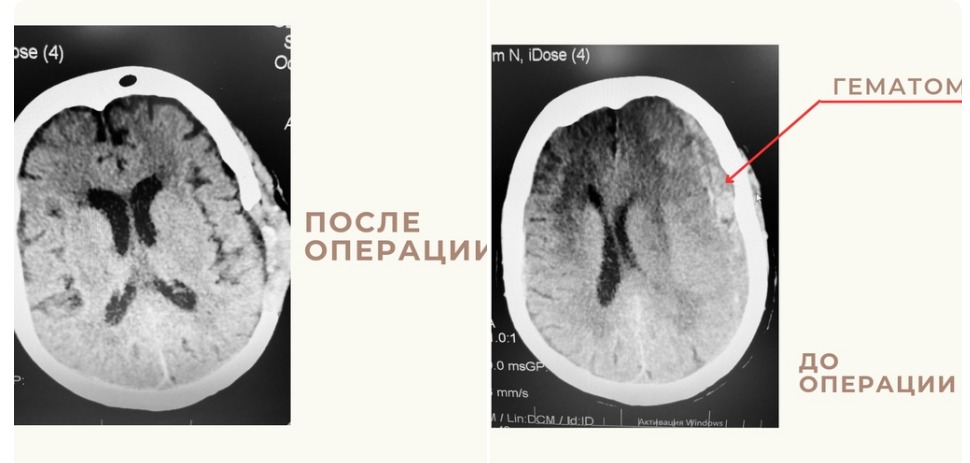

В отделение больницы имени Кирова была доставлена 86-летняя женщина в бессознательном состоянии с нарушением мозгового кровообращения. Время, когда пациентка потеряла сознание не известно. Компьютерная томография показала нетравматическую гематому в левой теменной области, отёк вещества головного мозга. Диагноз – тяжелый геморрагический инсульт.

Дежурная бригада врачей провела женщине экстренную операцию. В связи с большим возрастов пациентки состояние ее здоровья было отягощено сопутствующими заболеваниями.

После операции астраханку перевели в подразделение ГКБ №3 им. С. М. Кирова на проспекте Бумажников, в отделение реабилитационно-восстановительного лечения. Вследствие того, что женщина соблюдает все рекомендации врачей, за две недели произошли глобальные улучшения по состоянию здоровья – речевая функция и двигательная активность почти полностью восстановились. Совсем скоро пациентка сможет вернуться к нормальной жизни.